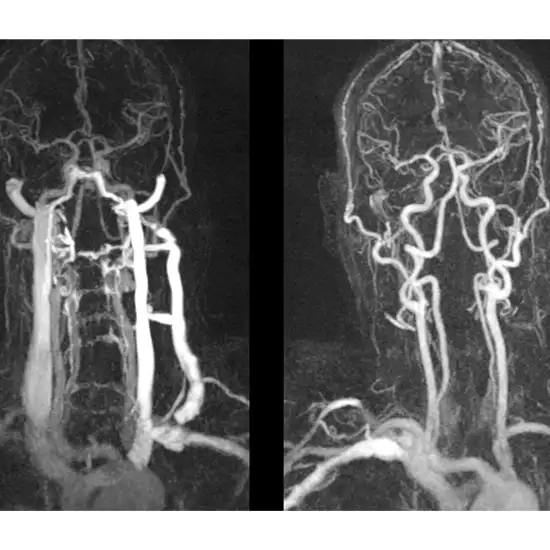

अस्पताल में डॉक्टरों ने तत्काल सिटी एंजियोग्राफी करवाई। रिपोर्ट देखकर खुद डॉक्टर भी हैरान रह गए। मरीज की दाईं कैरोटिड आर्टरी फट चुकी थी और वहां गुब्बारे जैसी संरचना बन गई थी। यह स्थिति बेहद खतरनाक मानी जाती है, जिसमें जान जाने का खतरा बहुत ज्यादा रहता है।

डॉक्टरों के अनुसार, इस तरह के मेडिकल केस दुनिया में बेहद कम देखने को मिलते हैं। अब तक ऐसे सिर्फ 10 मामले ही दर्ज थे। रायपुर में सामने आया यह केस दुनिया भर में इस तरह की घटनाओं का 11वां मामला बताया जा रहा है, जिसने मेडिकल जगत का ध्यान खींचा है।

रायपुर में एक दुकानदार ब्रश करते समय अचानक बेहोश हो गया। जांच में पता चला कि उसकी गर्दन की दाईं कैरोटिड आर्टरी फट चुकी थी। यह दुनिया के सबसे दुर्लभ मेडिकल मामलों में से एक है। समय पर सिटी एंजियोग्राफी और इलाज से मरीज की जान बचाई जा सकी।